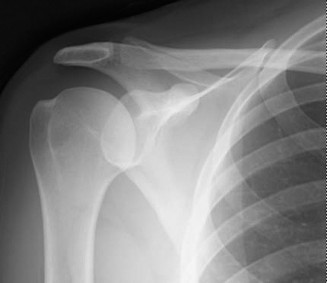

CASE 11 A 33-year-old male presents to the ED after a fall during a soccer game…